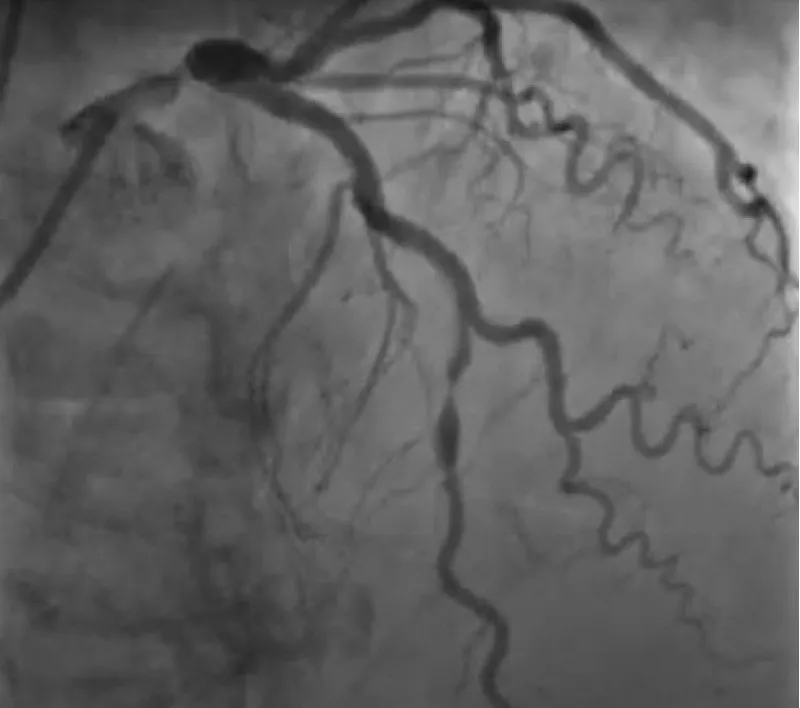

The clinical case concerns an 81-year-old woman with a history of systemic arterial hypertension, hypercholesterolemia, paroxysmal atrial fibrillation, chronic kidney disease, iron-deficiency anemia, and bilateral carotid atheromatosis for which she underwent a Carotid Endarterectomy (CEA) procedure. Additionally, she had a history of breast carcinoma, treated with surgery, subsequent chemotherapy, and ongoing Letrozole therapy. In 2019, the patient presented to the emergency department due to exertional dyspnea and low-threshold angina. During hospitalization, high average ventricular response (109 BPM) atrial fibrillation was diagnosed. Routine lab tests showed rising of hsTN-I (peak 800 pg/dL) and pro-BNP (peak 2476 pg/mL) and anemia Hb 9.1 g/dL. Echocardiography revealed severe depression of the left ventricular function (ejection fraction of 30%, with antero-apical akinesia) and low-flow-low-gradient aortic stenosis (mean gradient of 26 mmHg and AVAi of 0.5 cmq/m2 and SVi 29 mL/m2). So it was performed a Dobutamine stress Echo showed a rise of SVi up to 38 mL/m2 and a mean aortic gradient of up to 48 mmHg. Coronary angiography showed the right dominant coronary artery, of good caliber and course, with no angiographically significant lesions (Figure 1). The Left Main artery, with good caliber, had a 90% calcific stenosis at the distal segment, involving the proximal segment of the Left Anterior Descending artery. The Left Circumflex artery, with good caliber and course, presented a 30% ostial stenosis. The Intermediate Branch, with good caliber and course, showed 80% stenosis at the proximal segment (Figure 2). The Left Anterior Descending artery, also of good caliber and course, was diffusely atherosclerotic with a long, severely calcific 80% stenosis at the mid-distal segment (Figure 3). Therefore, the case was discussed by a multidisciplinary Heart team at our center. The STS score calculated indicated a mortality risk of 11.4%. Due to this high risk, surgical treatment was not considered, and the patient underwent a four-step percutaneous intervention. Before the intervention, a CT angiography was performed, revealing an aortic annulus area of 433.2 mm2, a perimeter of 75.3 mm, and a coronary height from the annulus of 10 mm. The right common femoral artery mean diameter was 6.1 mm2 and the external iliac artery was 8.4 mm2 with moderate tortuosity without significant calcification (Figure 4-6). Therefore, a 23 mm Edwards Sapien 3 valve was chosen. Our strategy consisted of 4 steps:

Figure 2: The Left Main artery, with good caliber, had a 90% calcific stenosis at the distal segment, involving the proximal segment of the Left Anterior Descending artery. The Left Circumflex artery, with good caliber and course, presented a 30% ostial stenosis. The Intermediate Branch, with good caliber and course, showed 80% stenosis at the proximal segment.

Figure 3: The Left Anterior Descending artery, also of good caliber and course, was diffusely atherosclerotic with a long, severely calcific 80% stenosis at the mid-distal segment.